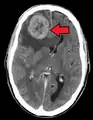

Initially, nearby lymph nodes are struck early.[9] The lungs, liver, brain, and bones are the most common metastasis locations from solid tumors.[9]

- Brain metastasis: neurological symptoms such as headaches,[9] seizures,[9] and vertigo[9]

Metastatic tumors are very common in the late stages of cancer. The spread of metastasis may occur via the blood or the lymphatics or through both routes. The most common sites of metastases are the lungs, liver, brain, and the bones.[10]